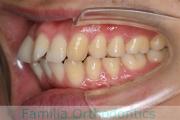

No.22V-029

- 叢生

- 上顎前突

- 19歳

- 男性

- 上:

- 8448

- 下:

- 主な使用装置:

- FEA 022

- 治療にかかった費用:

- 92万円

でこぼこを治したいということで来院されました。上下左右から親知らずも第一小臼歯も抜歯が必要で、歯科矯正アンカースクリューを併用して大臼歯を後ろに引っ張りながらの治療でした。3年弱、35回程度の通院が必要でした。

叢生が著しく、後戻りのリスクがあります。またアンカースクリューが必須のため、もしもスクリューが安定しないと、治療が難しく長くなってしまう恐れがありましたが、幸い脱落は見られませんでした。